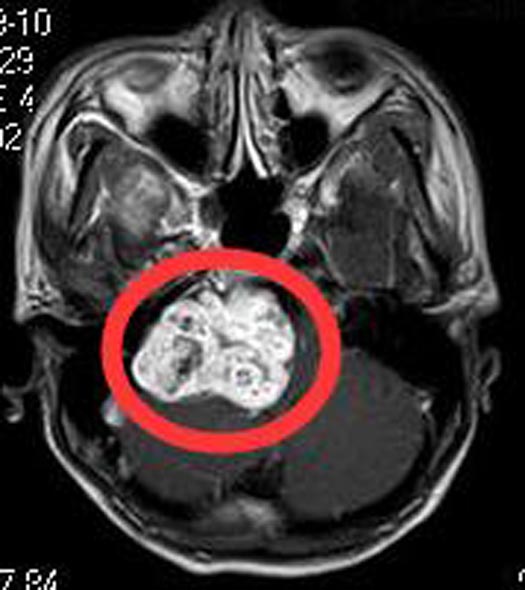

入住广东三九脑科医院综合神经外科,头颅MR检查结果:右侧桥小脑角区占位性病变4.5cm×3.6cm×5.7cm,增强后呈不均匀明显强化,向下达颈静脉孔区;邻近脑干、右侧桥臂及小脑半球明显受压移位。头颅CTA检查提示:右侧桥小脑角区肿块,突入右侧扩大的内听道,并沿扩大颈内静脉孔向颅外蔓延,其血供丰富,周缘较多血管缠绕,邻近椎基底动脉受压移位。